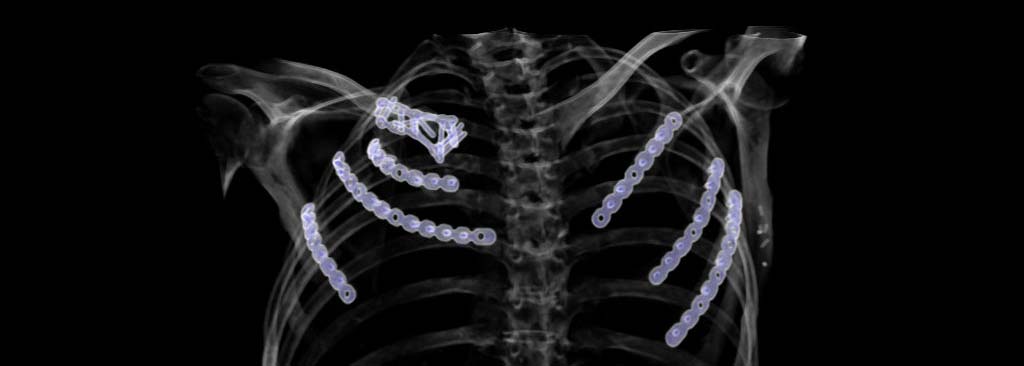

The ribs and the sternum protect the internal organs of the rib cage like a bone armor. For tumors of the chest wall, this must therefore be replaced. Bony malformations on the chest wall can lead to chronic pain, which is often difficult to diagnose and therefore often discovered late. Accidents and falls can cause serious injuries to the thoracic skeleton, which cause serious problems immediately after the accident or even some time later. Our department specializes in the diagnosis and treatment of bony thorax injuries.